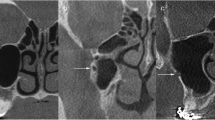

CT features

CT features included the tumor diameter, palatine or maxillary bone destruction, nasal cavity involvement, greater palatine foramen (GPF) enlargement, pterygopalatine fossa involvement, and foramen rotundum and cavernous sinus involvement (see Additional file 2). The average diameters of GPF on both sides in patients were determined by using horizontal level measurements, axial and coronal reconstruction was used when the horizontal level images were asymmetrical. As demonstrated by previous studies, there was minor variation (less than 0.2 mm) but no significant difference between the diameters of the left and right GPF [30, 31]. In this study, GPF enlargement was defined as a GPF diameter on the tumor side at least 0.3 mm larger than that on the normal side (Fig. 2). On the tumor side, compared with the normal side, any signs of abnormal density/signal intensity, contrast enhancement or widening of the nasal cavity, pterygopalatine fossa, foramen rotundum or cavernous sinus on the tumor side were defined as involvement. GPF enlargement, pterygopalatine fossa involvement and foramen rotundum involvement were defined as PNS signs at the same time. These criteria were consistent with those from previous studies [29, 32].

Computed tomographic images of cases with or without GPF enlargement. The diameters of the left and right GPFs were measured in bone window (upper layer: horizontal level; lower layer: coronal reconstruction). (a) No.35 patient was considered without GPF enlargement (GPF diameter on the tumor side was 0.2 mm larger than that on the normal side). (b) No.13 patient was considered with GPF enlargement (GPF diameter on the tumor side was more than 0.3 mm larger than that on the normal side). (c) NO. 71 patient was considered as GPF enlargement (complete destruction of GPF on the tumor side). GPF = greater palatine foramen